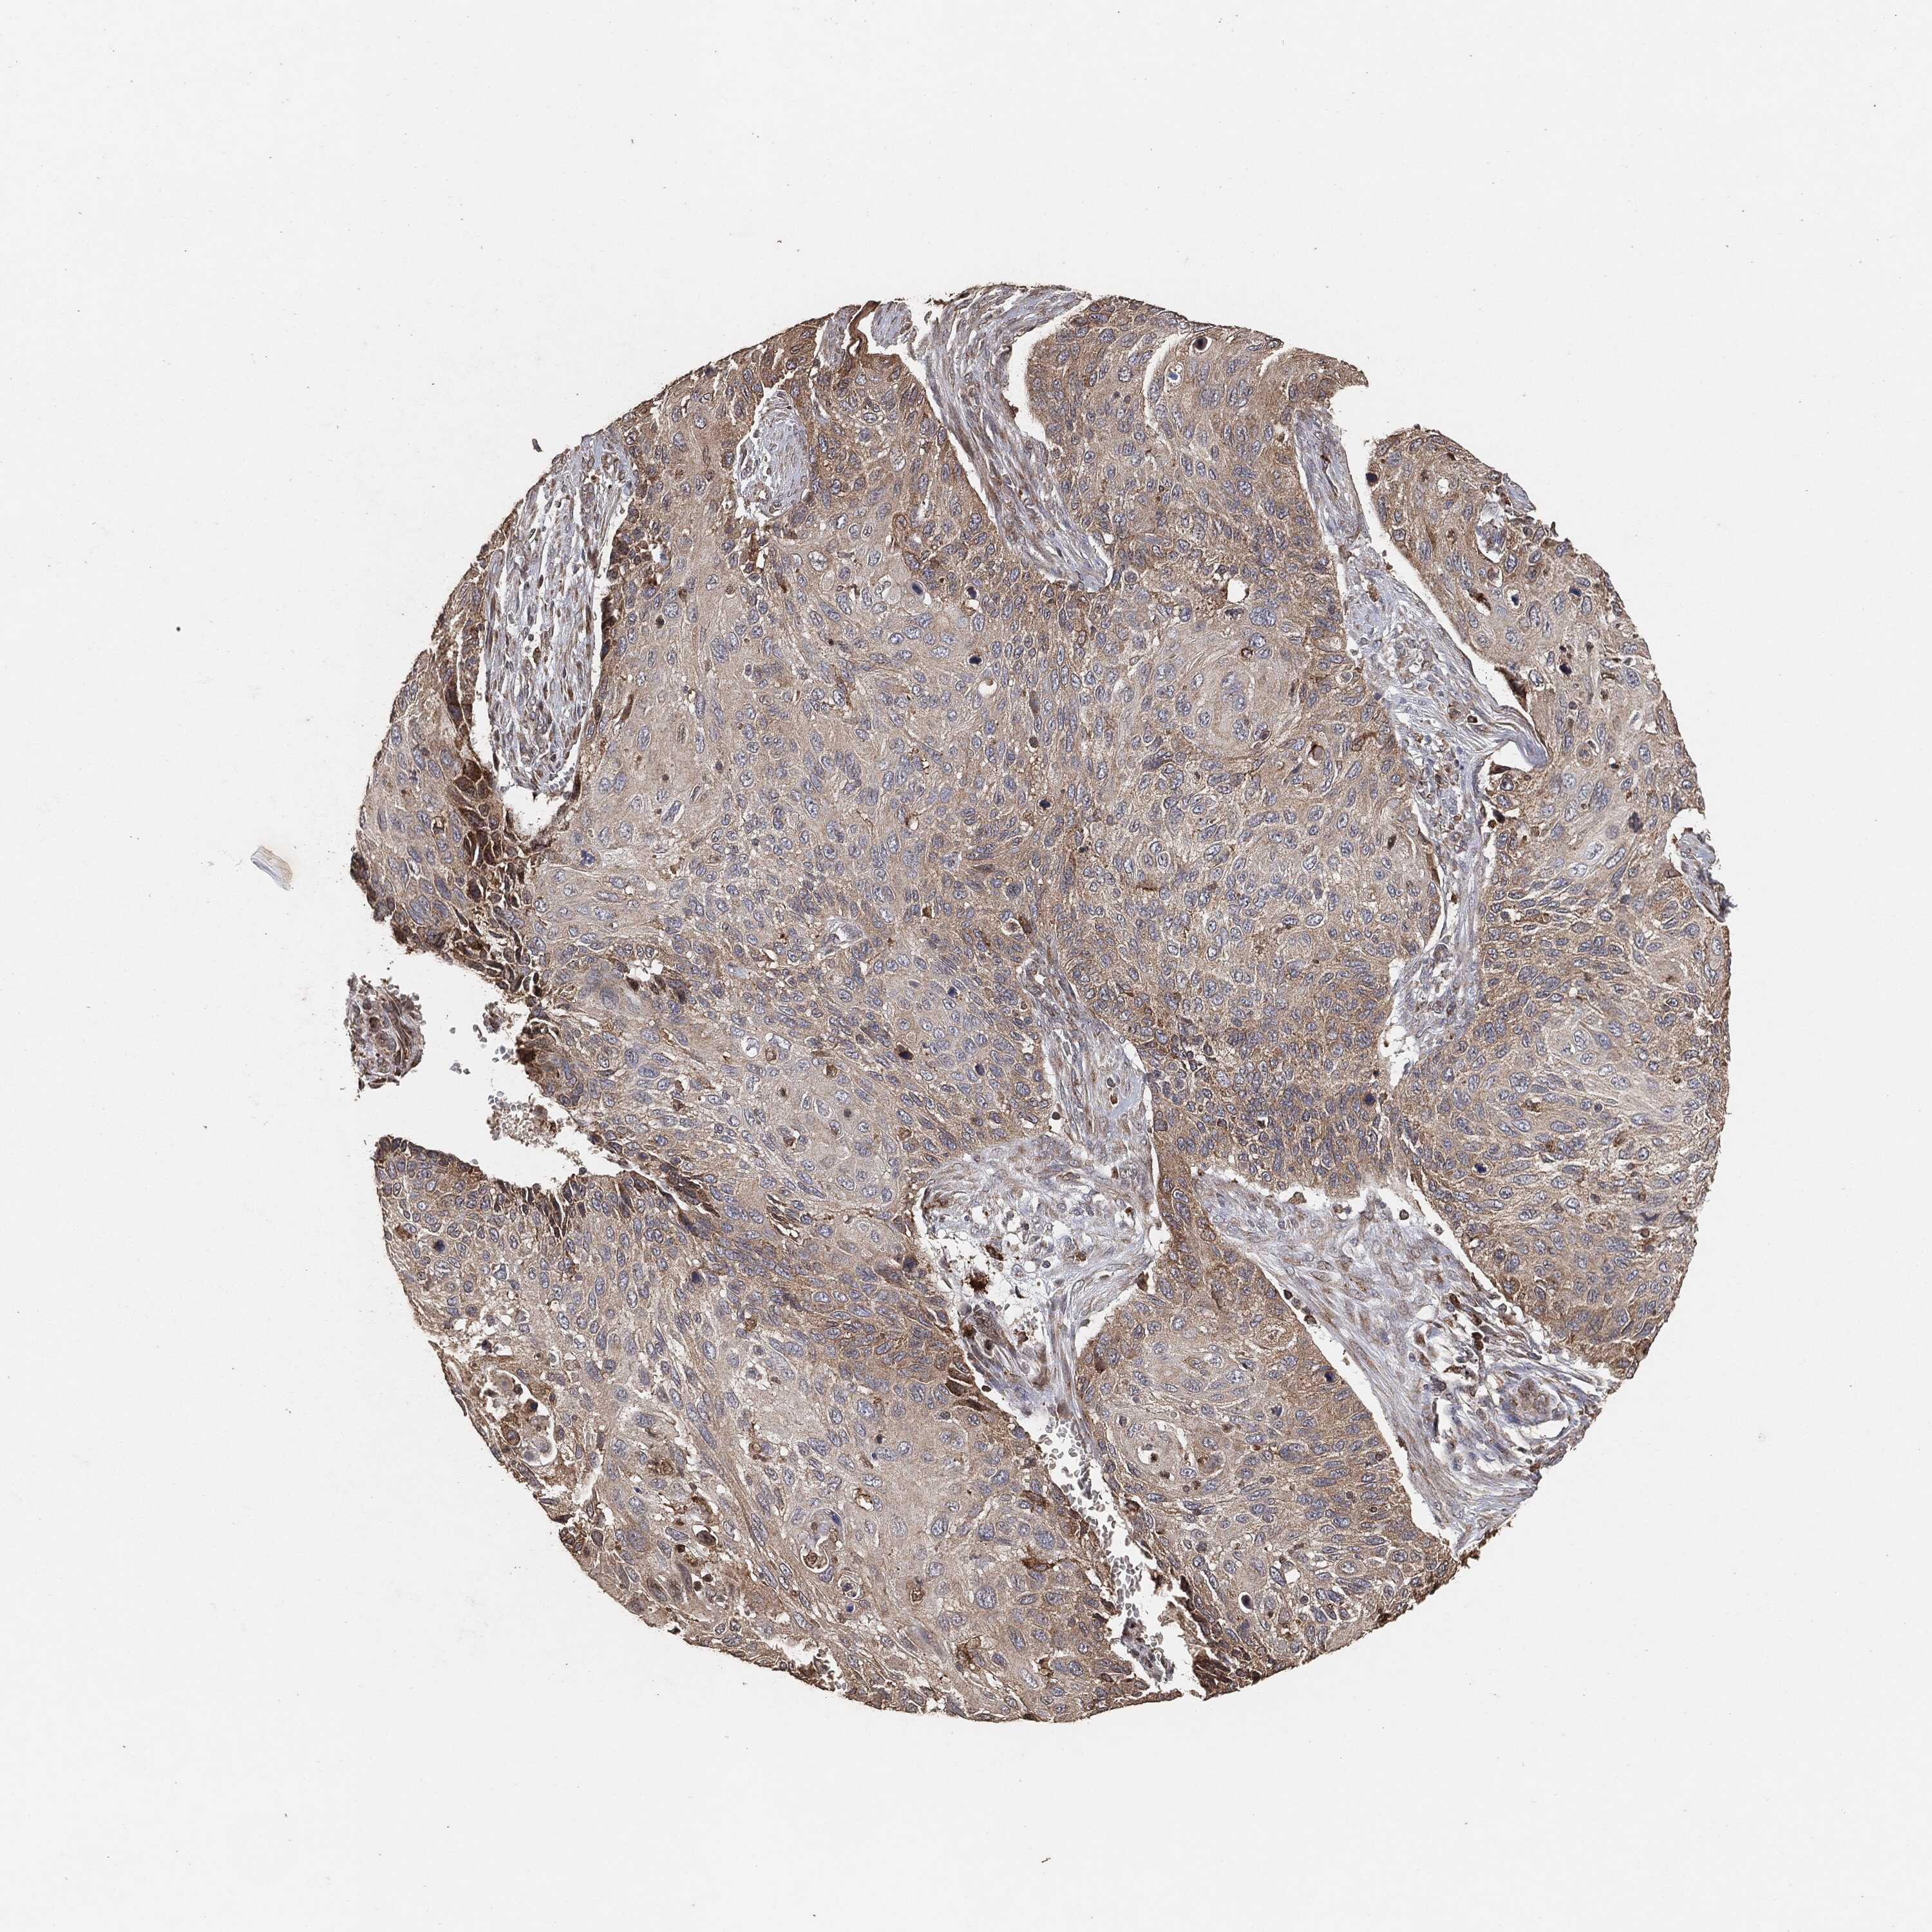

CERVICAL CANCER - Protein expressioni

A mouse-over function shows sample information and annotation data. Click on an image to view it in a full screen mode. Samples can be filtered based on level of antibody staining by selecting one or several of the following categories: high, medium, low and not detected. The assay and annotation is described here.

Note that samples used for immunohistochemistry by the Human Protein Atlas do not correspond to samples in the TCGA dataset.

Antibody stainingi

Antibody staining in the annotated cell types in the current human tissue is reported as not detected, low, medium, or high, based on conventional immunohistochemistry profiling in selected tissues. This score is based on the combination of the staining intensity and fraction of stained cells.

Each image is clickable and will lead to virtual microscopy that enables deeper exploration of all samples and also displays staining intensity scores, fraction scores and subcellular localization as well as patient and tissue information for each sample.